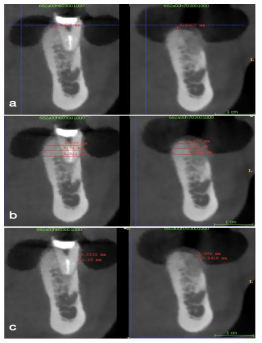

Figure 1 : Pictures of a clinical case using the One Piece autologous tuberosity graft technique (a) tooth #43 to be extracted due to lack of buccal bone and mobility (b) tissue punch being used in the right maxillary tuberosity site (c) bone trephine burr containing the One Piece graft (d) One Piece graft (e) fitting of the graft in the socket (f) placement of the graft inside the socket  (g) sutures to stabilize the graft (h) the grafted site 4 months post-op (i) implant placement 4 months post-op.